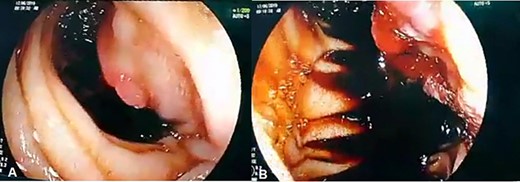

Admission work-up revealed anemia (hemoglobin = 7.8 g/dL, hematocrit = 23%). Emergent upper GI endoscopy showed active bleeding of ulcerated tumor on the third duodenal portion (Fig. 1A and B). Enhanced computed tomography (CT) scan revealed 5 × 4.5 cm hypervascular mass on the previous duodenojejunal anastomosis without metastasis (Fig. 2A and B). Diagnosis of locally recurrent duodenal GIST was suspected. Progressive anemia had developed in spite of transfusion 3 units packed red blood cells, and thus, emergent laparotomy was performed. During laparotomy, we found recurrent mass just on the previous duodenojejunal anastomosis without intraperitoneal or liver implantations (Fig. 3). A careful limited resection of the distal third part of the duodenum with proximal jejunum was carried out (Fig. 4). Side-to-side anastomosis between the second duodenal portion and jejunum was performed (Fig. 5A–C). Feeding jejunostomy tube was inserted. Post-operative course was uneventful. The patient was discharged on the ninth post-operative day. Histopathology report revealed 4 × 3 cm spindle cell type duodenal GIST, mitotic index < 5/50HPF, resection margins free more than 5 mm, intact pseudocapsule with vascular invasion and tumor emboli (Fig. 6A and B). Immunohistochemical staining for CD117 was positive (Fig. 6C). Unfortunately, molecular assessment of the recurrent tumor was unavailable in our institute. Adjuvant imatinib 400 mg/day was administered. To detect any recurrence in the liver or peritoneal cavity during adjuvant imatinib therapy, intensive surveillance with enhanced abdomen and pelvis CT scan every 6 months was recommended [3].

Enhanced CT scan (A) axial section and (B) coronal section: shows well enhanced mass 5 × 4.5 cm (arrow) at previous duodenojejunal anastomosis without intraperitoneal or liver metastasis.